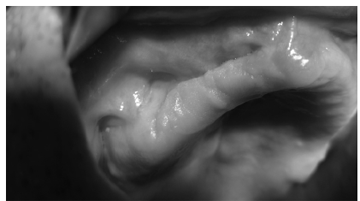

Решено произвести операцию, под общим обезболиванием: резекция области ОН верхней челюсти, ревизия верхнечелюстной пазухи справа. После обнажения кости верхней челюсти, была обнаружена четкая граница остеонекроза (рис.3). Произведена остеотомия некротизированного участка в пределах здоровых тканей (рис.4). После удаления некроти- зированного участка кости, открылось широкое сообщение с верхнечелюстной пазухой, в которой об-наружились полипозные разрастания и гной (рис.5). Были удалены патологически измененные ткани из верхнечелюстной пазухи, образовали сообщение с нижним носовым ходом, произвели тампонаду верхнечелюстной пазухи, вывели конец тампона через соустье, образованное с нижним носовым ходом. В конце, рана в полости рта была ушита наглухо (рис.6). Одновременно больному назначили антибиотики широкого спектра действия (отменили через 5 дней после операции) и местные антисептики.

Послеоперационный период протекал гладко . Тампон, из гайморовой пазухи, был удален через 2 дня, швы были удалены через 10 дней. При повторном осмотре через 2 месяца, больной жалоб не предъявлял. В области вмешательства, цвет слизистой оболочки без особенностей, определялся небольшой дефект альвеолярного отростка верхей челюсти (рис.7). Пальпация области вмешательства безболезненна, заметен тонкий послеоперационный рубец.